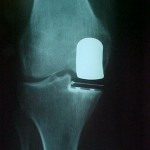

Entre un 20 y un 40% de los procesos degenerativos de la rodilla son tributarios de tratamiento con cirugía protésica unicompartimental. Son artrosis donde existe un buen stock ligamentario tanto colateral como de LCA y LCP.

Normalmente son rodillas arqueadas, es decir, con una deformidad que se denomina genu varo y el dolor se refiere a la parte interna de dicha rodilla.

La prótesis unicompartimental preserva el stock de hueso. Se practica mediante una incisión pequeña sin pérdida hemática (no precisa transfusión sanguínea), con estancia hospitalaria de 24 horas. En caso de afectación de ambas rodillas, la cirugía puede practicarse simultáneamente en ambas. El paciente marcha a su domicilio caminando.

Este tipo de cirugía protésica además no cierra la puerta a otras posibles actuaciones futuras, siendo un aspecto muy importante cuando se habla de implantar una prótesis en una articulación tan importante como la rodilla.